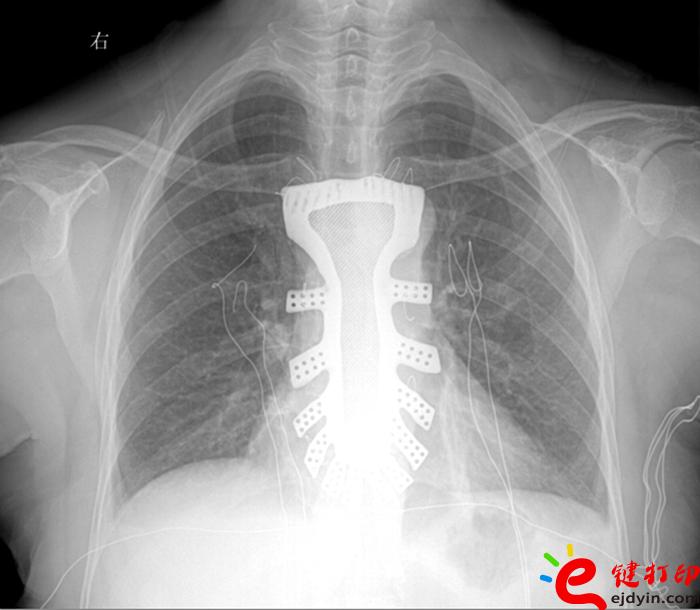

当然,“3D打印”的世界远不止如此。据参加大会的专家和企业负责人介绍,目前“3D打印”已被运用在文化创意、文物修复、生物医疗、工业设计等多个领域。如,在航空航天器材上,一些关键零部件采用“3D打印”一次成型,使得其功能更加实用,重量大幅减少;在医疗领域,“3D打印”被运用于牙齿再造和骨骼修复等方面,从而使治疗更加精准。